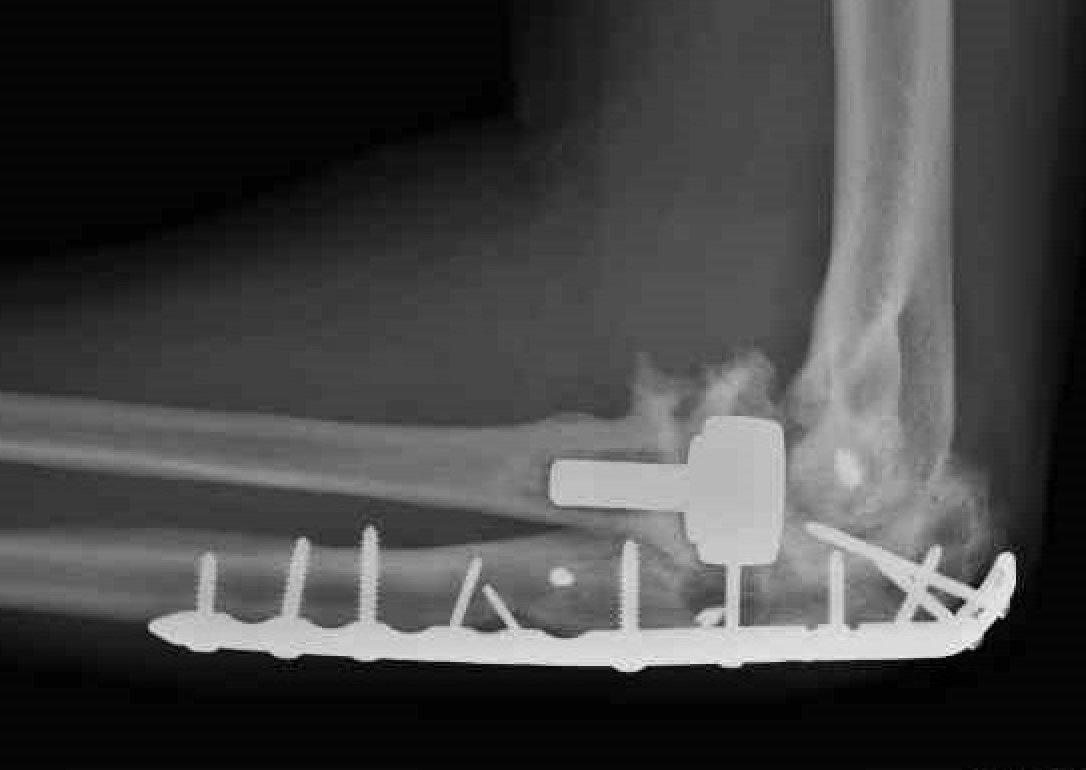

Olecranon plate + ORIF Type II coronoid process + radial head replacement

Olecranon plate with radial head replacement

Olecranon plate with radial head replacement + LCL repair

Olecranon plate + medial coronoid buttress plate + radial head replacement

Complex proximal ulna fracture with radial head replacement subluxation